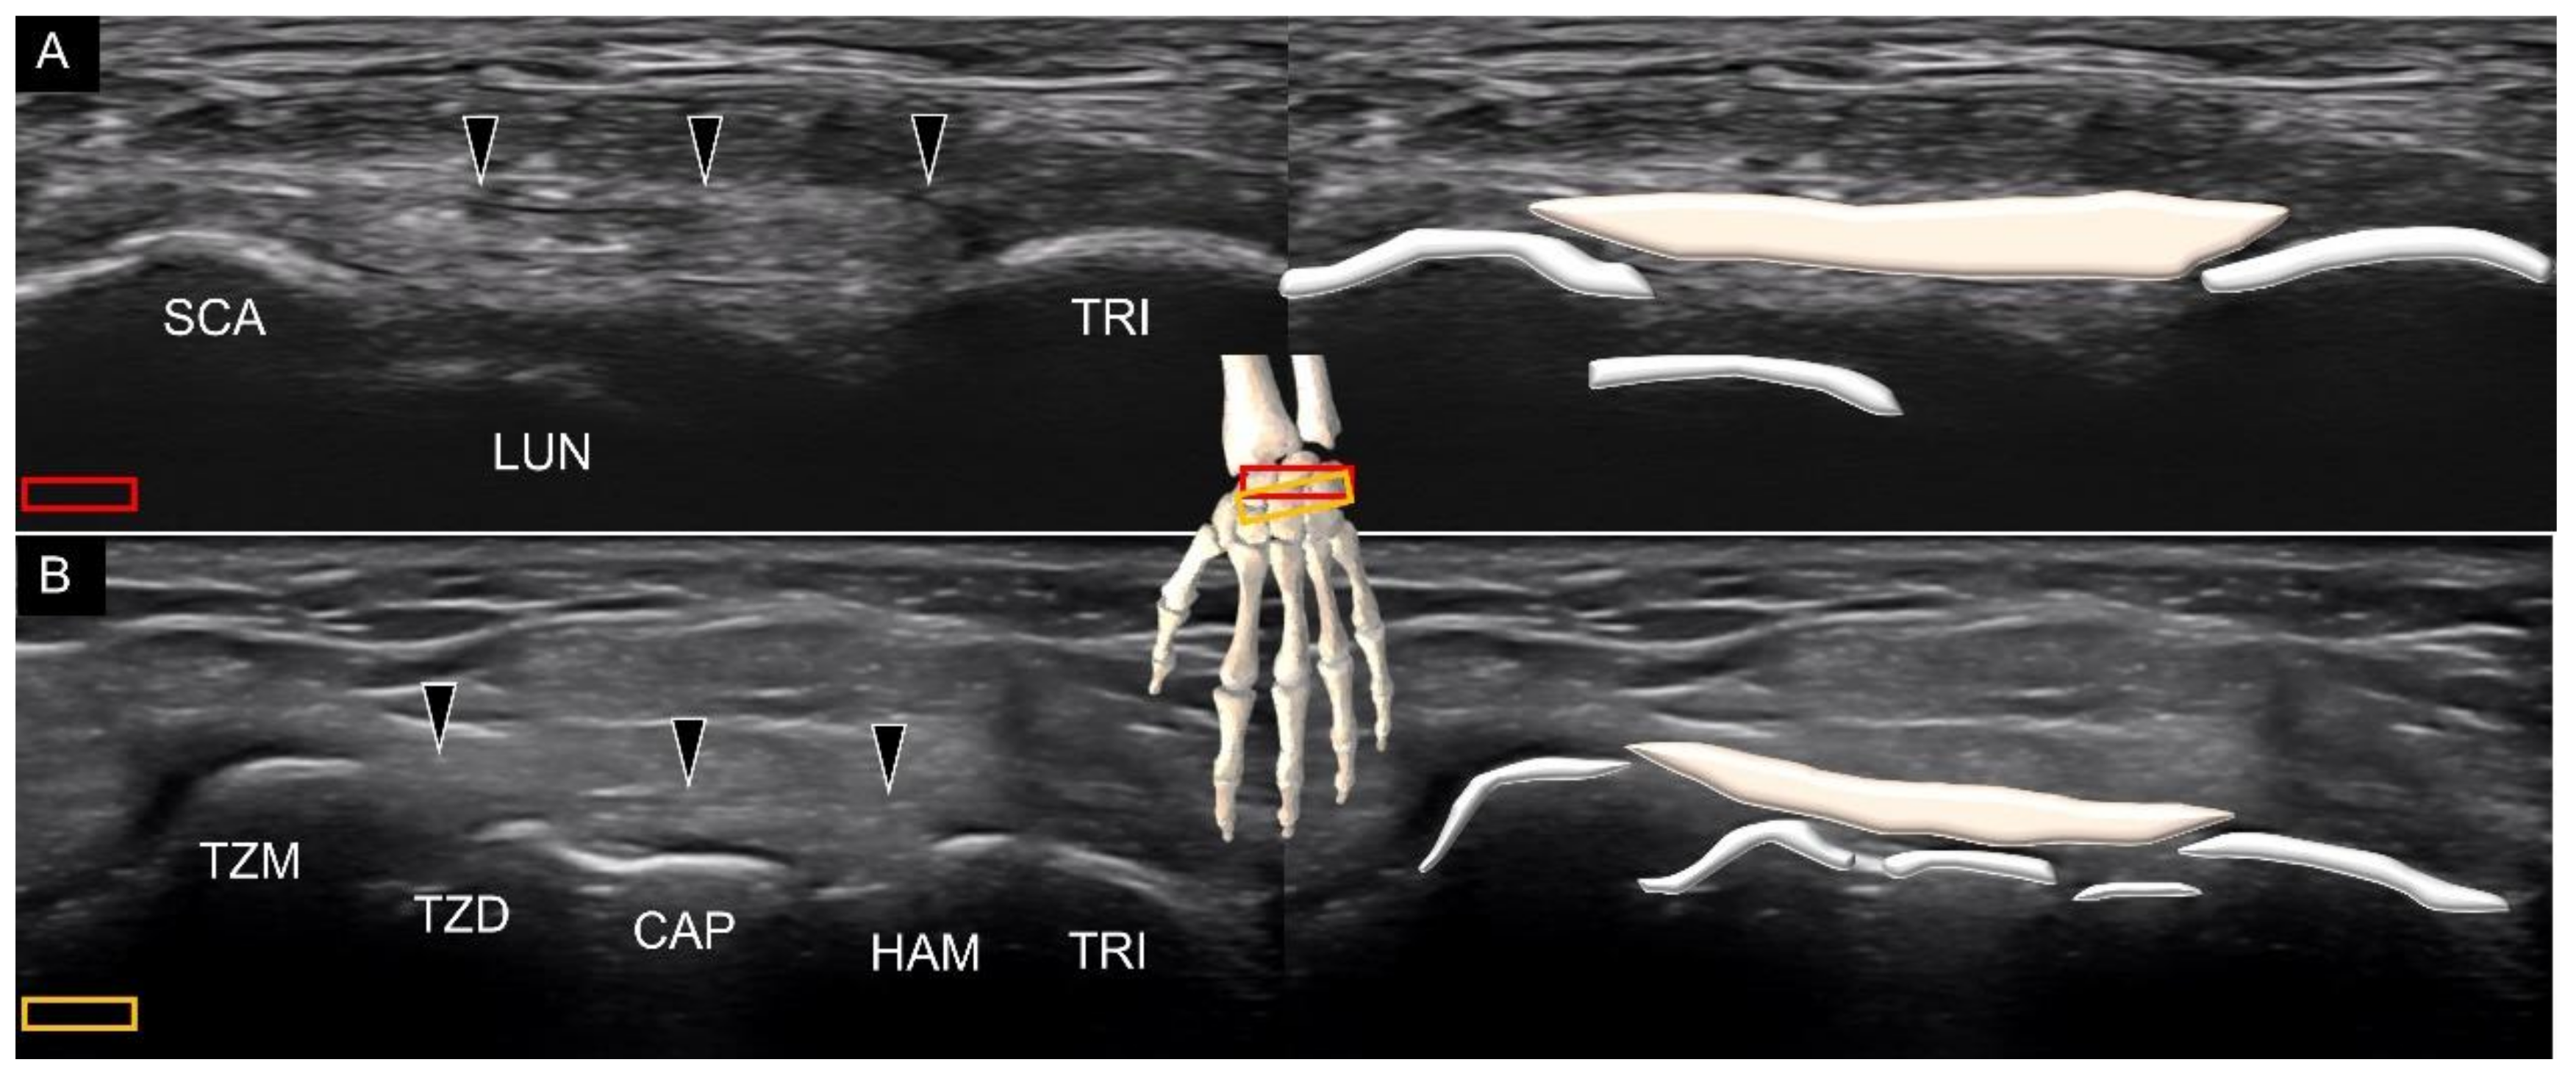

3.1. Attachment to the Capitate

3.2. Attachment to the Lunate

Attachment to the Triquetrum

6. Sonoanatomy of Dorsal Intrinsic Carpal Ligaments